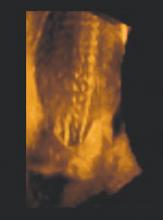

4D ultrasound of an open neural tube defect in a developing fetus

Folic acid supplementation. If your patients are like most women, they may not be aware of the importance of folic acid supplementation. Yet by neglecting to supplement their diet with folates, women are passing up an opportunity to reduce the incidence of neural tube defects (NTDs) such as anencephaly and spina bifida by up to 70%.4

Women considering conception or those who do not use contraception should take 400 mg folic acid, a dosage found in most prenatal vitamins, every day. All women of reproductive age should consider folate supplementation because of the high rate of unplanned pregnancies. Women who have previously had a child with an NTD and women who take anti-epileptic drugs should take 4 mg folate per day.5